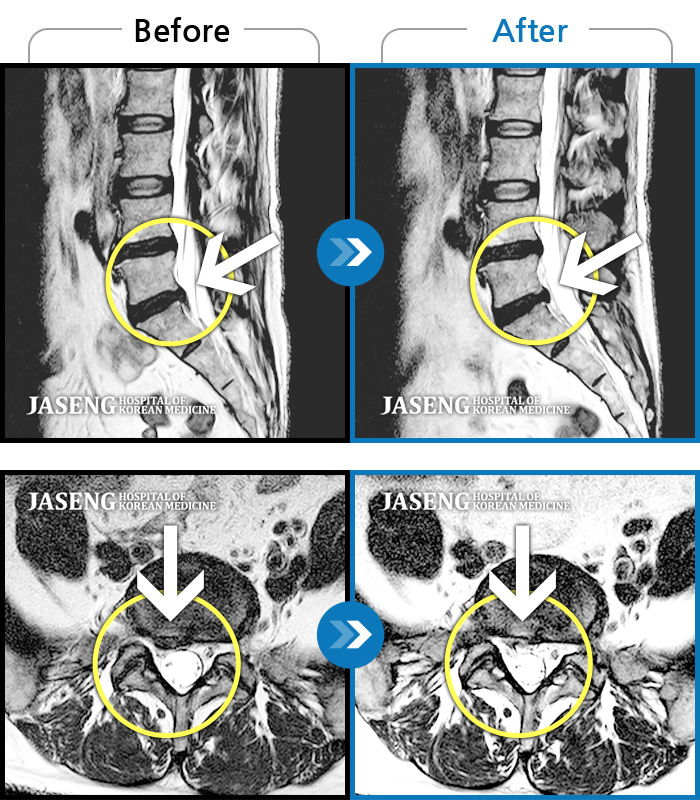

허리디스크

천안 · 윤영웅 원장

허리와 좌측 다리 통증저림이 심하고 발목 힘이 빠져요.

촬영시기

2021.09.17 ~ 2022.04.30

2022.05.02

조회수 146